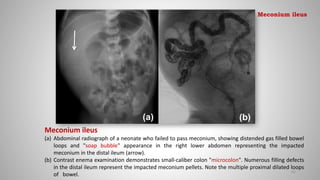

Meconium ileus

(a) Abdominal radiograph of a neonate who failed to pass meconium, showing distended gas filled bowel

loops and "soap bubble" appearance in the right lower abdomen representing the impacted

meconium in the distal ileum (arrow).

(b) Contrast enema examination demonstrates small-caliber colon "microcolon". Numerous filling defects

in the distal ileum represent the impacted meconium pellets. Note the multiple proximal dilated loops

of bowel.